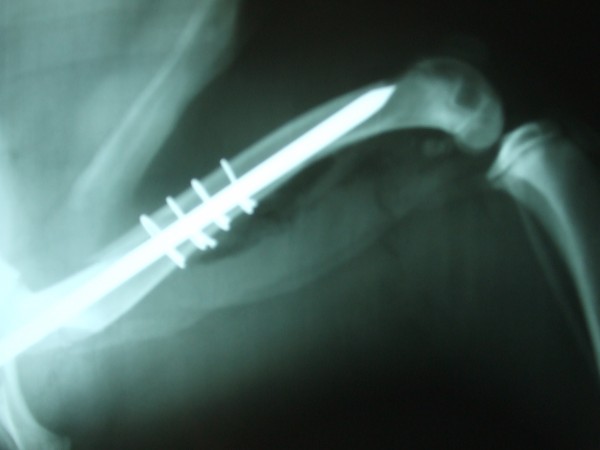

Ortopedia